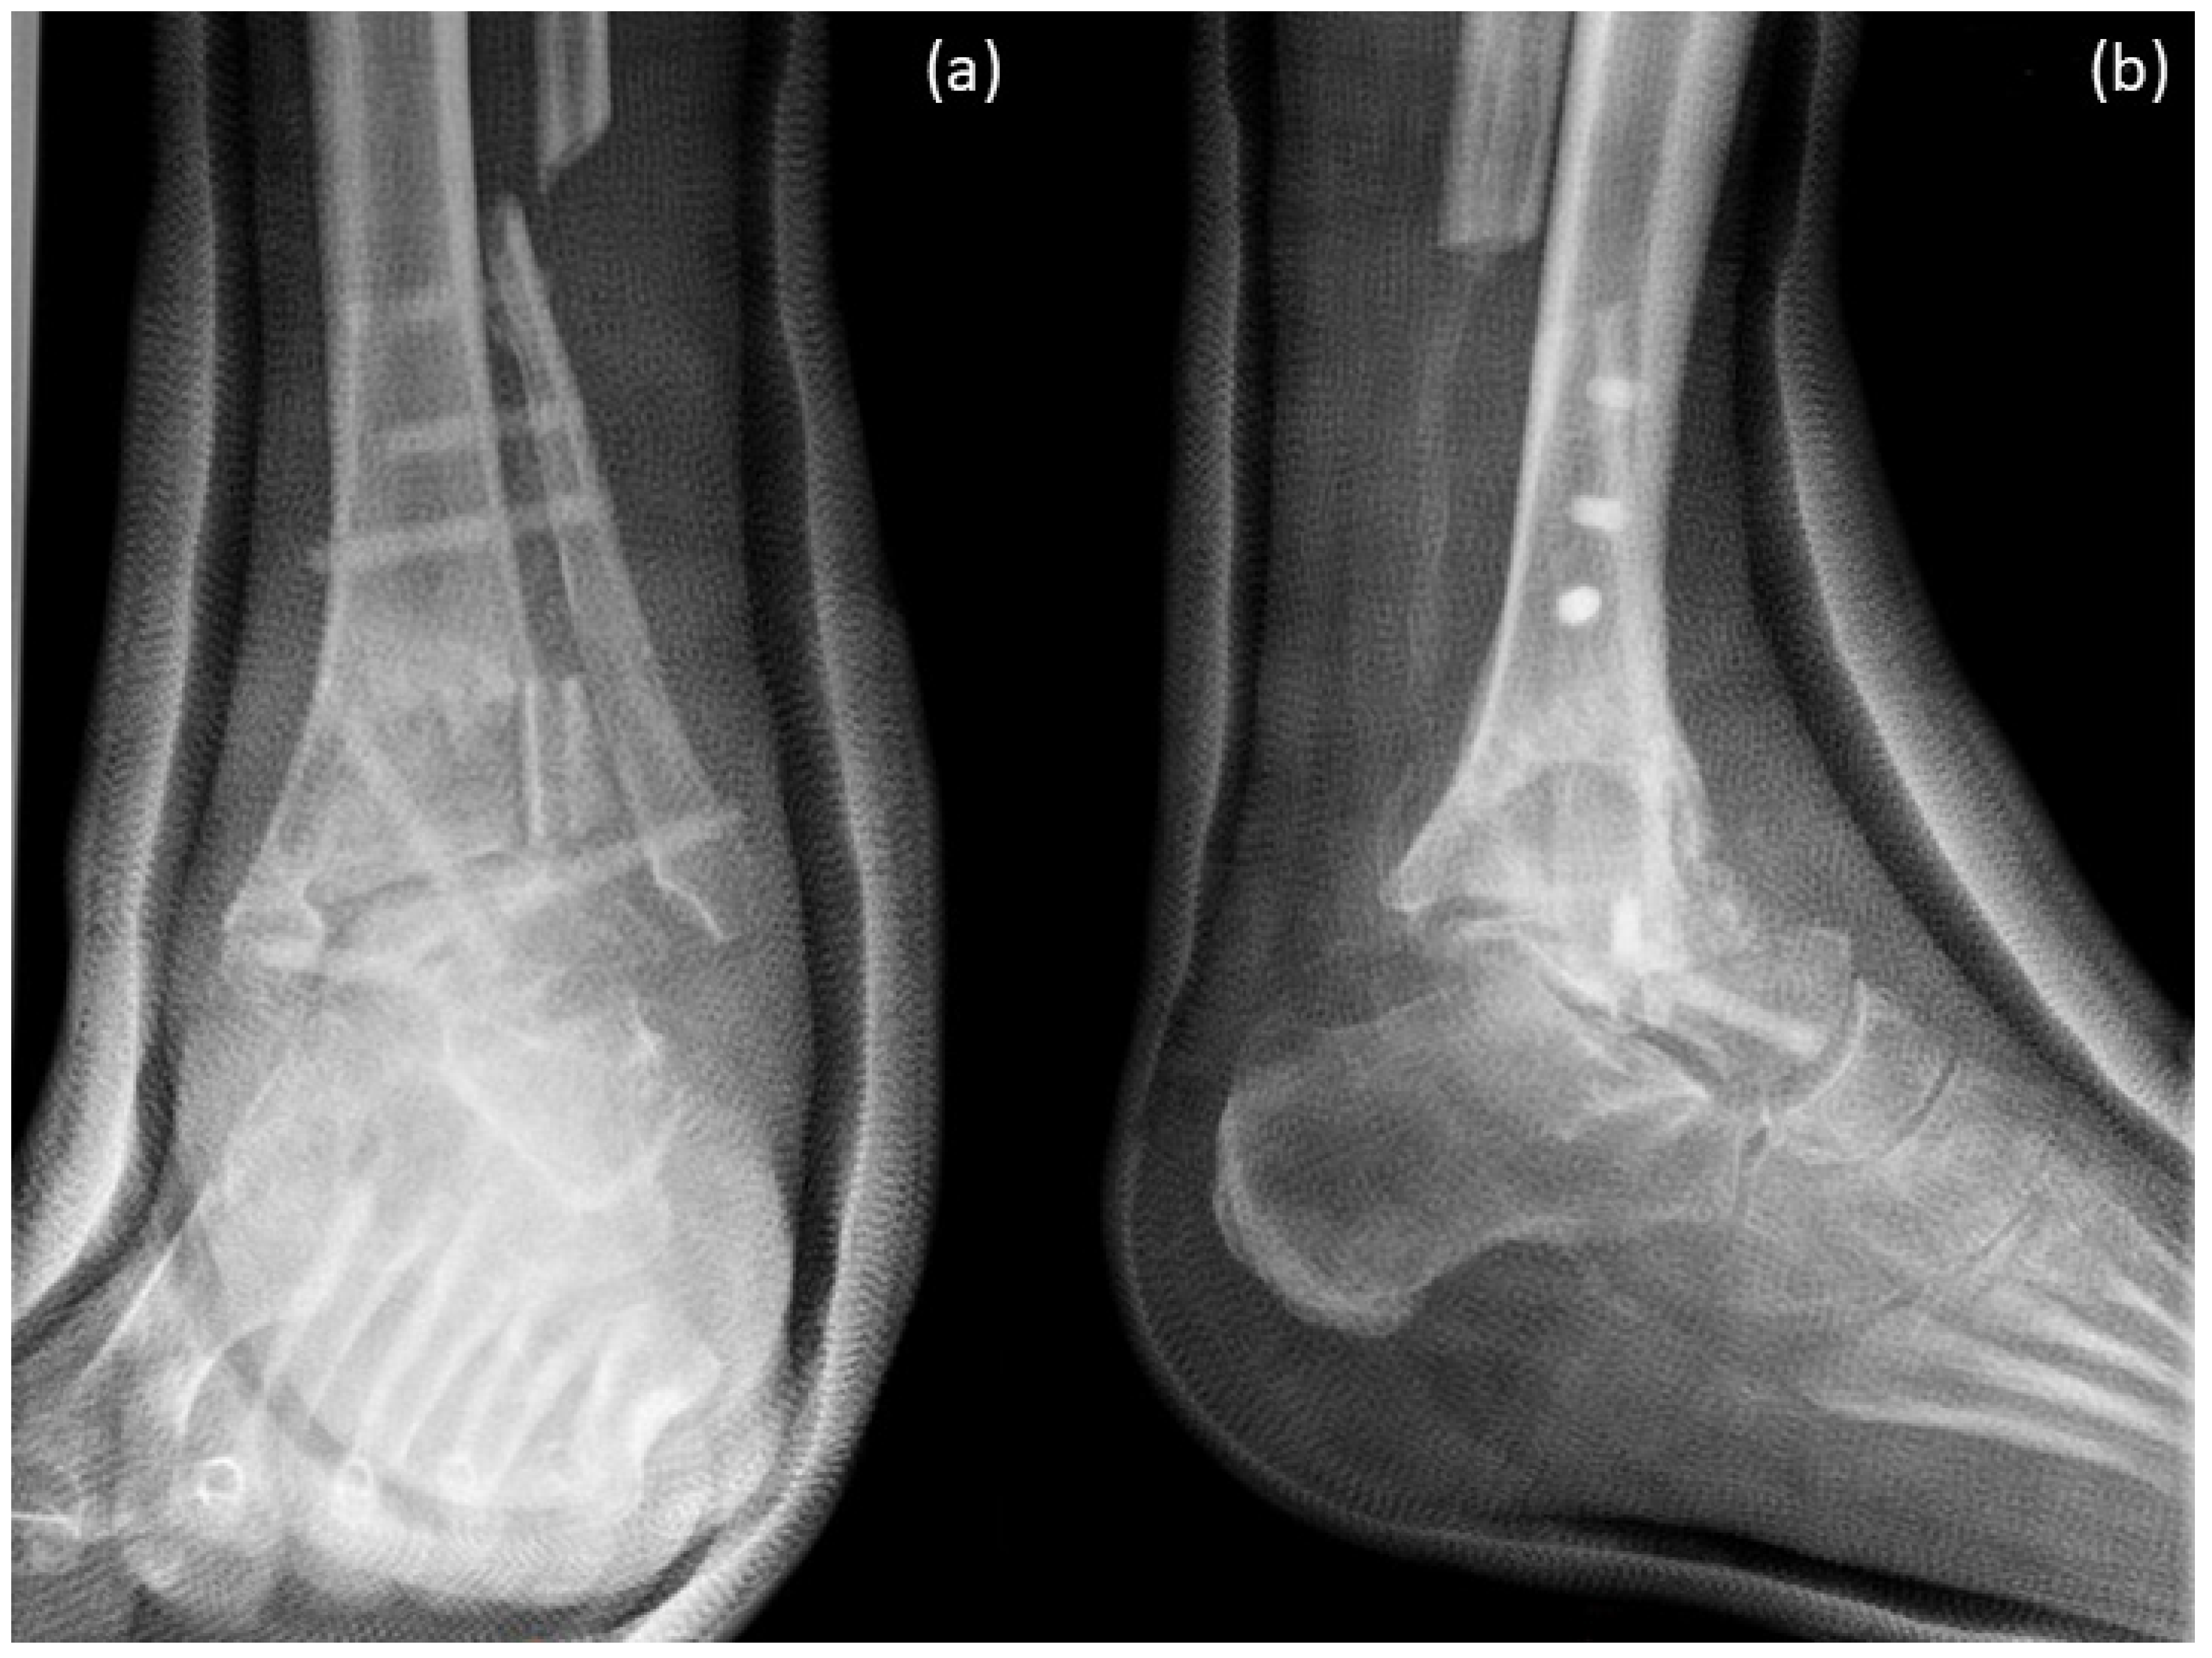

Figure 8.

X-rays just after surgery. Arthrodesis was performed with 6 Shark Screws® and a huge amount of allograft (femoral head and tricortical chip). (a) Ap-view; (b) lateral view.

X-rays were performed just after surgery, 12 weeks and 1 year after surgery. Figure 8 shows X-rays just after surgery. Arthrodesis was performed with 6 Shark Screws® and a huge amount of allograft (femoral head and tricortical chip).